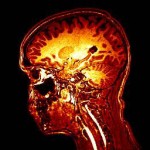

30 Januari 2010: Als proefpersoon in de MRI scan

8 maart 2010: Ontvangst hersenscans

Daar stonden dan eindelijk mijn hersenscans ingepakt in een pakketje in mijn postvak-in! Ja zeker 3D beelden! Na snel wat programma’s als MRICron en MRIcro te installeren kon ik al snel door mijn brein heen scrollen. Van craniaal naar caudaal, dorsaal naar ventraal en van lateraal naar lateraal. MRIcron hield me nog wel even zoet.